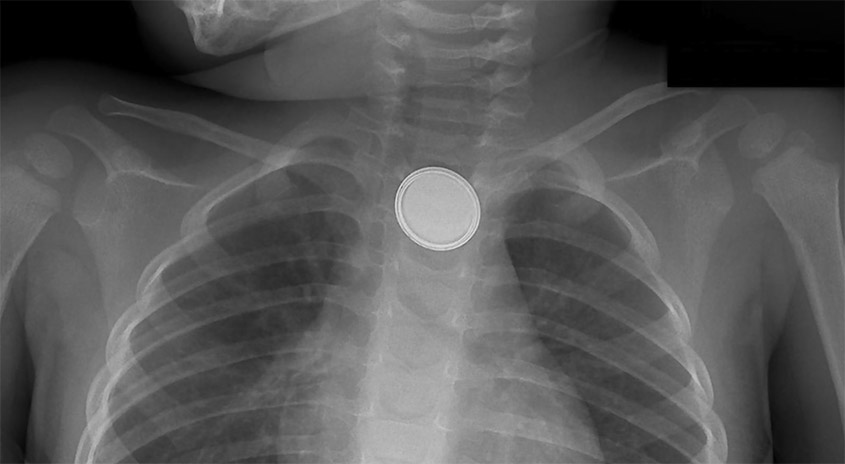

Ein Röntgenbild zeigt eine Münze, die in der Speiseröhre einer Person steckt, mit sichtbaren Rippen und Schlüsselbeinen.

Wenn eine verschluckte Lithium-Knopfzelle in der Speiseröhre stecken bleibt und

nicht entfernt wird, kann das eine schädliche chemische Reaktion auslösen und schon

innerhalb von zwei Stunden tödlichen Folgen haben. Wenn du denkst, dass dein Kind

eine Batterie verschluckt hat, ruf umgehend einen Rettungswagen oder fahre sofort in eine Notaufnahme!